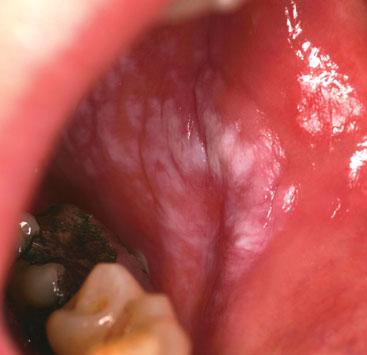

LICHEN PLANUS

Oral lichen planus manifests as a raised white rash on the buccal mucosa. In this image there are plaques but sometimes there may be striae (Wickham), ulcers, papules or redness. The condition may be associated with skin manifestations of the condition and 25% women will develop genital lesions whereas less than 5% men will be affected in this way. Drugs such as beta-blockers, ACE inhibitors and NSAIDs may cause a lichenoid eruption. Symptoms may range from none to pain. For the latter, topical steroids may be helpful. Follow-up is important to exclude the small risk of the development of cancer.